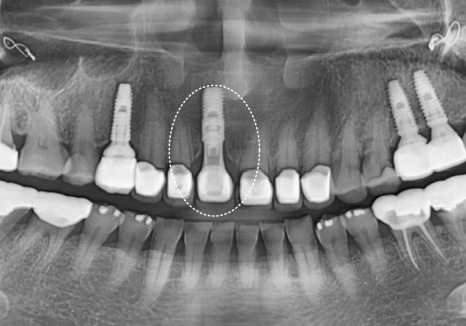

4개월 뒤,, 환자분께서 다시 내원하셨는데요.

식사 도중 앞니 하나(#11)가 부러져 오셨어요.

안타깝게도 뿌리만 남아

임플란트가 필요했습니다.

부러진 앞니(#11), 치료 계획

고덕동 앞니 보철, 브릿지와 싱글 크라운, 어떤 선택이 나에게 더 유리할까?

뿌리만 남은 앞니는 우선 발치를 진행했는데,

다행히 CT 상 잇몸뼈가 아주 튼튼한 상태였어요.

240628

덕분에 번거로운 뼈이식 과정 없이

그날 바로 임플란트를 심어드리는

즉시 식립이 가능했습니다.

그렇게 두 달 정도 시간이 흘러

임플란트와 뼈가 단단하게 잘 붙은 것을 확인하고,

이제 그 위에 올릴 치아머리를

만들 차례가 되었습니다.